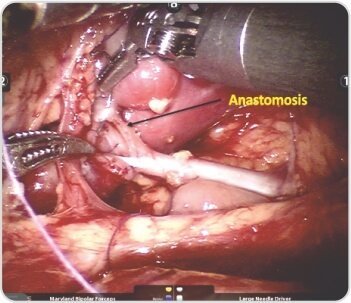

Robotic left-sided Uretero-Pyelostomy was done. Dilated upper moiety ureter was transected and anastomosed to lower moiety pelvis in end to side fashion. DJ stent was placed across the anastomosis into the upper moiety ureter. Post operative period was uneventful and the stent was removed after 6 weeks.